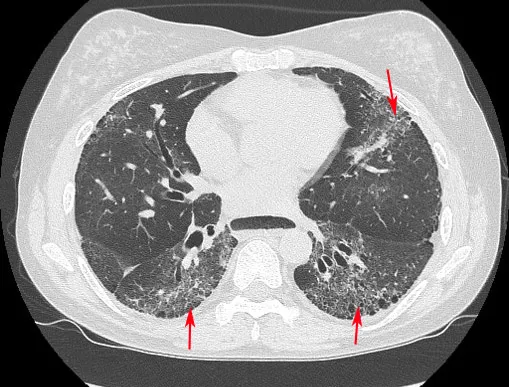

初期症狀是在天冷或接觸冰冷物體時,手指會變白或變紫,回暖後恢復紅潤,稱作雷諾氏現象。隨著病情進展,皮膚逐漸變硬、變緊,內臟器官也可能出現纖維化,導致呼吸急促、胃食道逆流,甚至引發肺纖維化和肺動脈高壓等嚴重併發症,肺纖維化是病人最主要的死亡原因,因此及早診斷治療並找出高風險族群至關重要。

全身硬化症合併肺纖維化(箭頭指處)。中榮提供